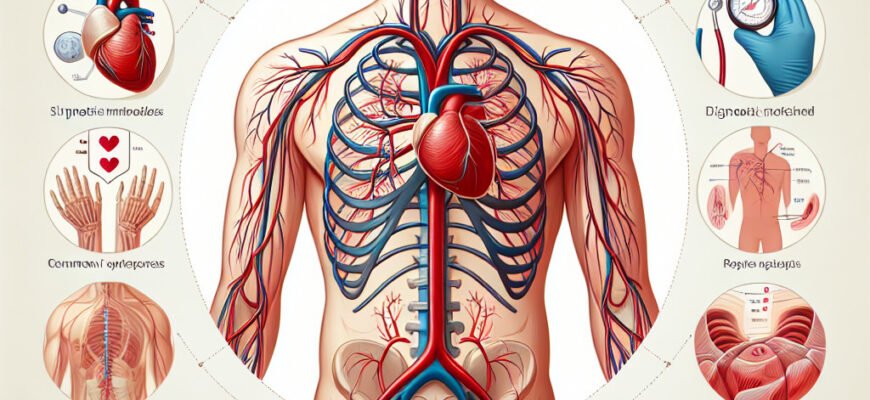

Синдром верхньої брижової артерії (SVBA) – це неподобство, що вміщує у собі і біль, і дискомфорт, і багато незрозумілого. Це не є найпоширеніше медичне явище, тому багато з нас взагалі не знає, з чим маємо справу. Але коли цей синдром стає вашою реальністю, він здатний змінити ваше життя. Тож, про що йдеться? Розбираємось далі.

Уявіть собі, що частина вашого шлунково-кишкового каналу стикається із проблемою кровопостачання. Саме це відбувається при SVBA. Це коли верхня брижова артерія, яка постачає кров до значної частини кишкового тракту, стискається чи стискаються навколишні тканини, що впливає на орган. І це лише початок.

Симптоми SVBA нагадують лабіринт. Через це діагноз встановити важко. Проблема? Біль у животі, втрата ваги, нудота. Їм байдуже, чи у вас свято, чи буденний день – вони просто приходять.

Анатомія – гра без правил. І коли в неї втручається щось не те, всі гвинтики йдуть за своїм сценарієм. SVBA найчастіше трапляється у випадках швидкої втрати ваги, анатомічних вад чи навіть внаслідок травм. Звучить занадто складно? Може бути.